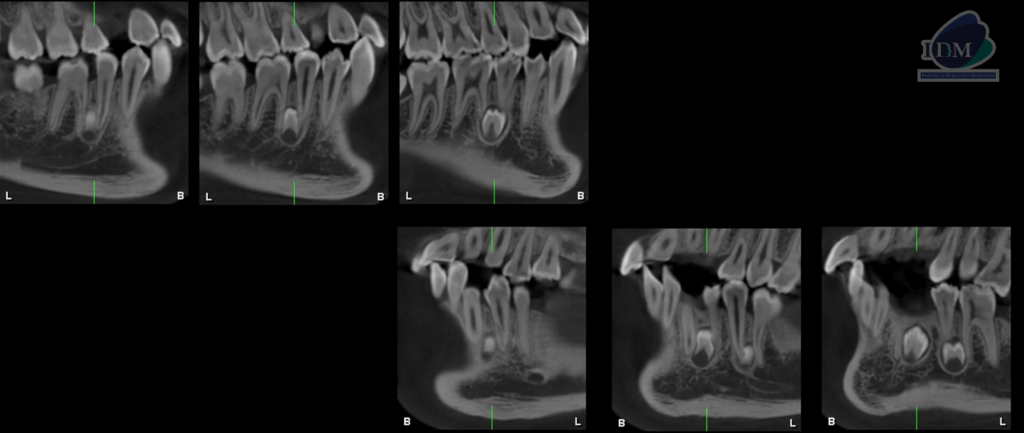

Así mismo en la tomografía volumétrica de haz se evidencia:

- Supernumerario 1: retenida en posición vertical y en contacto con los segmentos radiculares de las piezas 45 y 46, a nivel apical y orientado hacia lingual.

- Supernumerario 2: retenida en posición vertical y en contacto con los segmentos radiculares de las piezas 33 y 34, a nivel apical y orientado hacia lingual.

- Supernumerario 3: retenida en posición vertical y en contacto con los segmentos radiculares de las piezas 35 y 36, a nivel apical y orientado hacia lingual.

CORTES TANGENCIALES

CORTES TRANSAXIALES